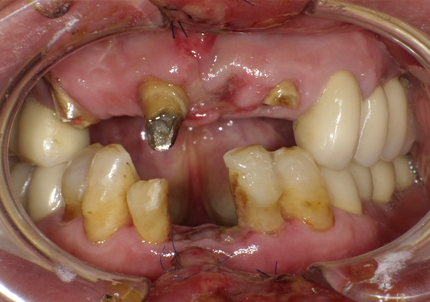

1.初診時口腔内写真(2018年10月)

1.初診時口腔内写真(2014年6月)

通院患者様が自転車転倒事故にて前歯5本破折や脱落の受傷する(2018年5月17日)

(受傷翌日来院時口腔内外写真)

受傷前の口腔内写真(2012年8月6日 前歯部治療終了時写真)